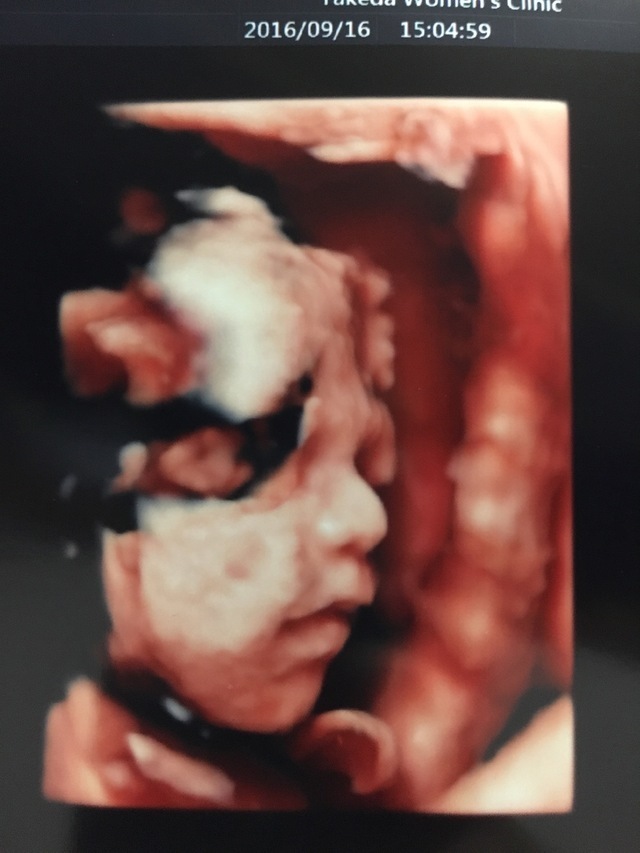

27週3日(27w3d・女の子)|saa1230 さん(19歳)

エコー写真撮影時のエピソード:

この時のエコー写真は初めてはっきりと顔を見せてくれた時のエコー写真です。

先生と一緒にエコーを見ていて、その時にちょうどあくびをしていたのをよく覚えています。とてもかわいくて先生と、看護師さんと3人でかわいい~♡とお話していました。